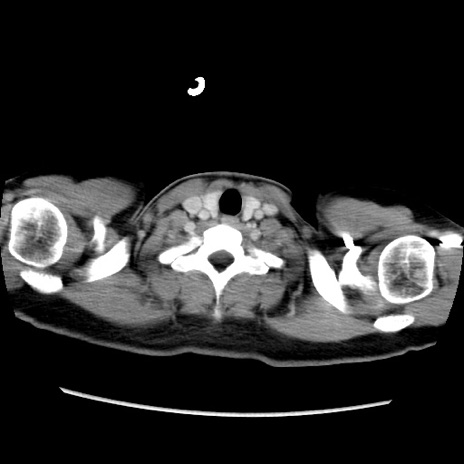

症例39(横断像)

【症例】40歳代女性

【主訴】上下腹部痛

【現病歴】2日目から下腹部痛あり。夜間は痛みで眠れなかった。昨日より上腹部痛と下痢が出現。臥位で痛みは軽快したため、休んでいた。本日になって臥位でも立位でも痛みが強くなってきたため救急要請。

【既往歴】子宮内膜症

【身体所見】部:平坦・軟、左上下腹部に圧痛あり、反跳痛あり。

【データ】WBC 21800、CRP 26.78